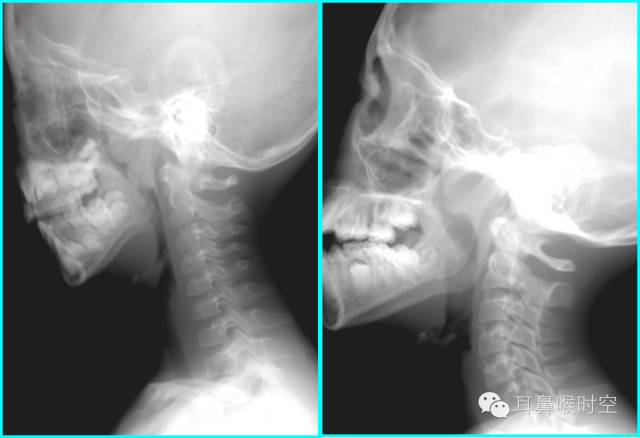

鼻咽部侧位X片的摄片方法

体位:患儿端坐或站立侧位,下颌略抬高,以减少下颌支与鼻咽腔重叠,眶耳线平行于地面,头颅矢状面与摄片架平行。

中心线:通过外耳孔前下方约2cm处。

注意:嘱患儿闭口用鼻吸气并摄片,防止软腭抬高造成鼻咽腔变窄的假象。